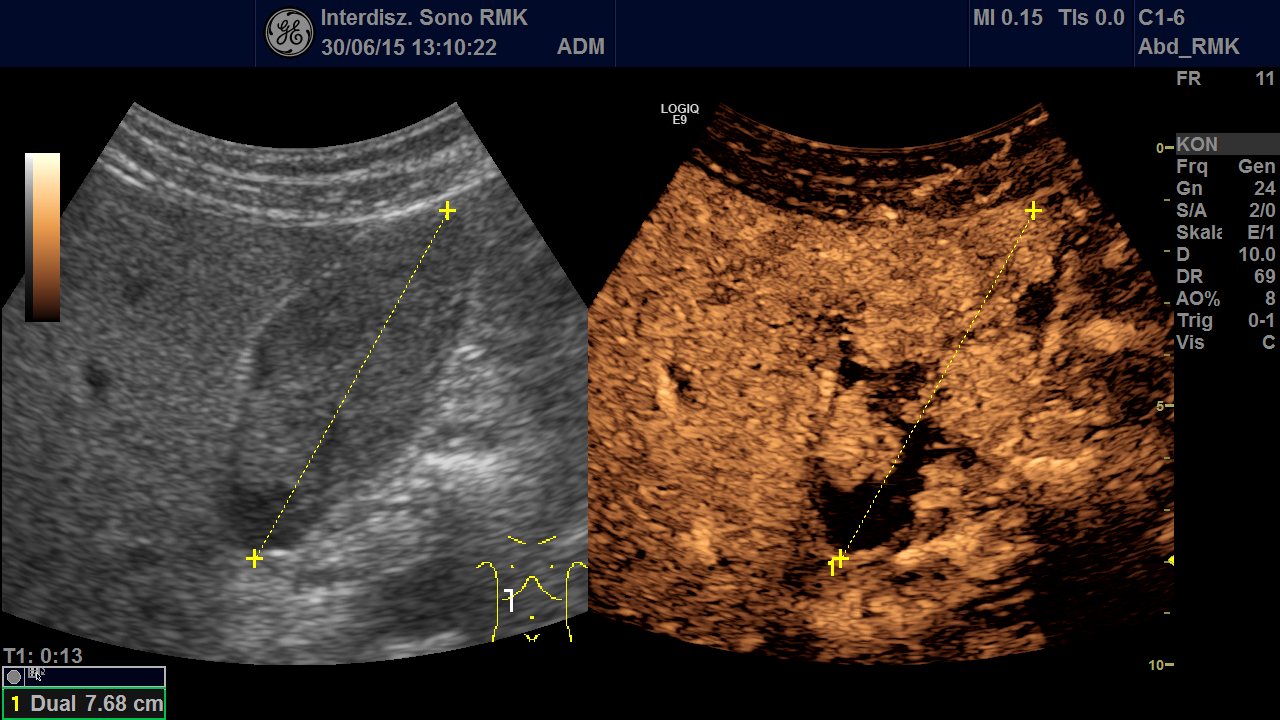

A 61 year old man was admitted to our hospital due to acute GI-bleeding. The man had been completely healthy until than and did not need any medications. One year ago a small melanoma on the head had been removed in toto. Routine ultrasonography before endoscopy showed echogenic material in the gallbladder (Fig. 1 + 2, Video 1). First gallbladder sludge was suspected. Because of its inhomogeneity in an additional linear array examination and a Doppler examination performed. Here arterial vessels in the gallbladder lumen were detected, thereby proving solid tissue (Video 2).

In addition, a contrast study (CEUS) was performed: This showed multiple polypoid tumors in the gallbladder lumen with strong contrast enhancement in the arterial phase and rapid washout (Fig. 3 + Video 3). Thus the echos in the gallbladder were no sludge but an intraluminal tumor! Only CEUS revealed the extend of tumor masses filling nearly the complete gallbladder.

Figure 2: Second look using the linear array: Note the inhomogeneity of the echos in the lumen. Left side position does not cause any changes. Also note the well preserved wall of the gallbladder.

Figure 3: CEUS (arterial phase 13 sec after bolus injection): powerful arterial contrast enhancement in multiple polypoid lesions in the lumen of the gallbladder. This proves neoplastic tissue and rules out simple sludge.